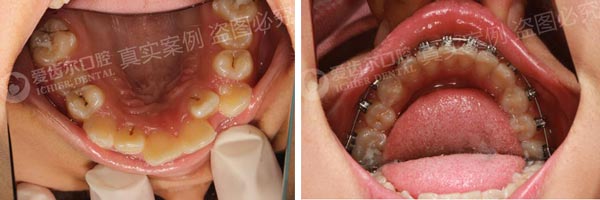

擅长儿童、青少年及成人各类错颌畸形的矫治(如“牙不齐”、“牙歪”、“嘴巴突”、“哨牙”、“小下巴”、“地包天”等),尤其擅长隐形矫正、直丝弓、功能矫治技术、舌侧矫正。